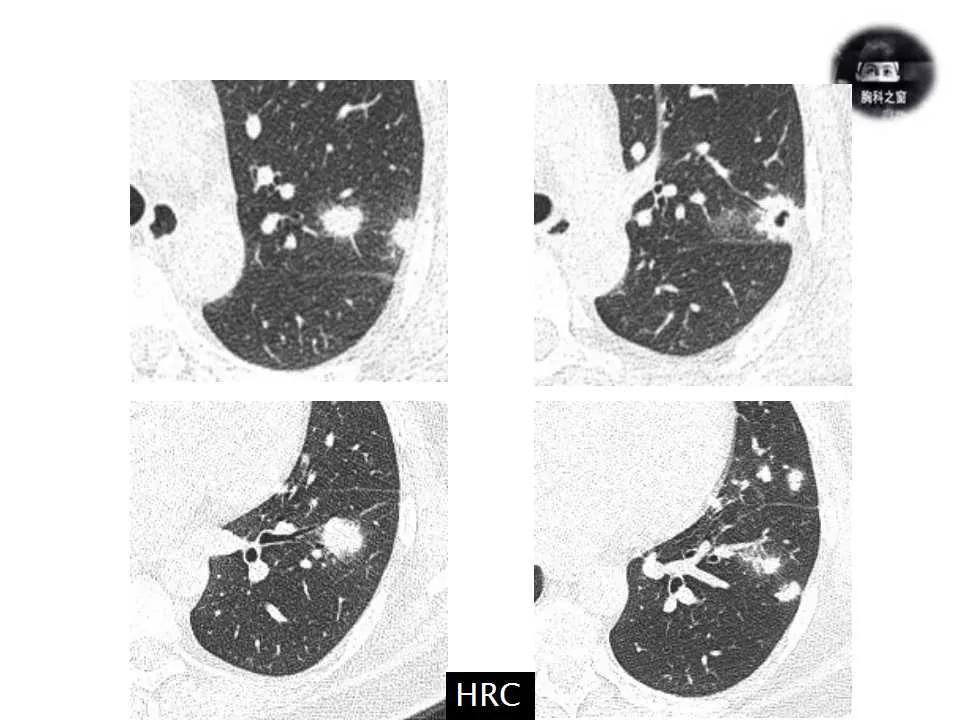

影像诊断:真菌性肺炎,隐球菌可能性大。

追问病史,有近距离接触鸽子史。隐球菌抗原(+)。

肺隐球菌病

3、肺隐球菌病可以通过CT引导下经皮肺穿刺、经支气管镜肺活检或外科手术肺活检等手段取得病理标本而诊断。黏蛋白卡红染色为隐球菌病的一种特殊染色,在病理组织中,有时可以看到一个界限清楚的透明区域,即为酵母的荚膜结构。